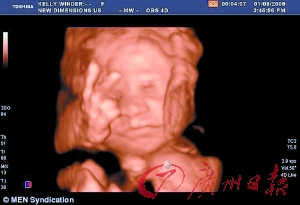

英国27周胎儿摆出不雅手势?

本报讯据英国媒体11月9日报道,一个27周未出世的胎儿竟然会做反“V”(在英国代表粗鲁、羞辱的意思)手势?近日,英国一名怀孕27周的妈妈前来皇家普雷斯顿医院进行胎儿检查,竟然发现自己尚未出世的孩子欧文在子宫里向上竖起两个指头,其他指头全缩起来,摆出了代表粗鲁的手势。

这种婴儿罕见的滑稽姿势让当地医院的工作人员一阵兴奋和欢闹。稍后,医务人员经孩子父母同意,将扫描图片公开(见上图),让其他人一同“观赏”。由于欧文的父母已有两个3岁大的女儿,孩子的父亲老欧文开玩笑地说:“这孩子长大会不会对姐姐不恭敬?还是表明我这还未出世的孩子已经知道了自己有两个姐姐?”